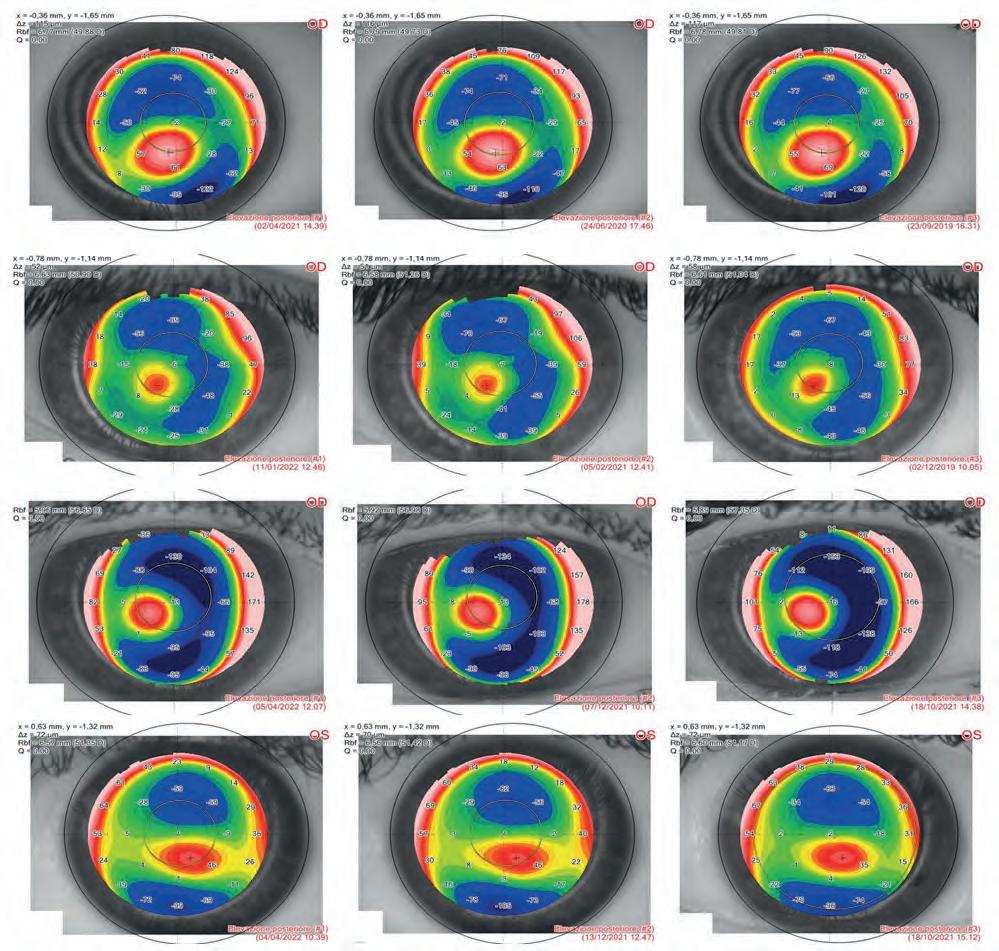

Le mappe differenziali refrattive (Figura 3) e tangenziali (Figura 4) mostrano il pattern di l'ablazione guidata con ray-tracing, e la relativa riduzione postoperatoria della point spread function (PSF) con il relativo miglioramento della qualità visiva (QoV) simulata, Figure 3 e 4.

Il valore medio di K max preoperatorio era 49,07 ± 0,9 D mentre il valore medio di K max era ridotto a 46,43 ± 0,7 D. Le differenze sono state considerate statisticamente significative con P ≤ 0,05. Il valore medio del COMA preoperatorio era 0,67 ± 0,09 µm; il valore COMA medio era dimezzato a 0,35 ± 0,02 µm. Le differenze sono state considerate statisticamente significative con P ≤ 0,05 sia per il K max che per la COMA, Figura 5.

Il valore medio del cilindro tomografico preoperatorio era -3,27±1,55 diottrie (D) ed è stato ridotto a -2,14±1,30 D. Le differenze non sono state statisticamente significative, tuttavia la riduzione della COMA comporta una riduzione del cilindro in quanto si elimina parte dello pseudo-cilindro di origine aberrometrica. Lo spessore corneale medio minimo (MCT) medio preoperatorio era 467,60 (intervallo 421–509 µm) e l'MCT medio postoperatorio era 401 µm (intervallo 351–440 µm). L'elevazione posteriore preoperatoria media è stata di 56,80 ±1,3 µm. L'elevazione posteriore postoperatoria è stata di 58,80 ±1,2 µm. La differenza non è risultata statisticamente significativa

(P > 0,05), mostrando stabilità durante l'intero periodo di follow-up. Il potere pupillare medio (MPP) preoperatorio era 47,27 ± 0,5 D; l'MPP postoperatorio è stato ridotto a 44,20 ± 0,6 D. Le differenze sono state considerate statisticamente significative con P ≤ 0,05. La densità delle cellule endoteliali non ha mostrato alcuna riduzione statisticamente significativa rispetto alla conta media delle cellule al basale da 2622±31 cellule/mm2 a 2597±39 cellule/mm2 Le mappe di follow-up dell'elevazione posteriore

mostrano la stabilità postoperatoria dell'ectasia nel tempo nonostante l'ablazione come dimostrato dalla Figura 6.

La mappa di ray-tracing del potere corneale totale dimostra una chiara regolarizzazione della cornea nel postoperatorio valutata con Precisio 2, Figura 7.

Figura 5. Il valore medio della COMA preoperatorio di 0,67 ± 0,09 µm mostra una riduzione statisticamente significativa (P ≤ 0,05) a 0,35 ± 0,02 µm

6. Le mappe di follow-up dell'elevazione posteriore mostrano la stabilità postoperatoria dell'ectasia nel tempo nonostante l'ablazione stromale selettiva